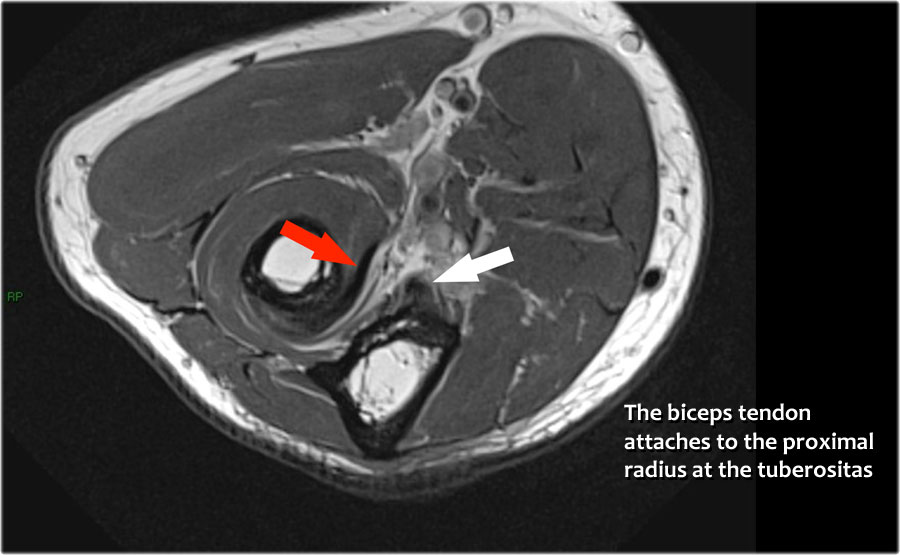

Biceps tendon

Attaches on the radial tuberosity.

Cuộn qua các hình ảnh cắt ngang của gân cơ nhị đầu từ chỗ nối cơ-gân đến điểm bám tận trên lồi củ xương quay.

Bệnh lý của gân cơ nhị đầu đoạn xa rất giống với bệnh lý của gân Achilles.

Có thể gặp thoái hóa gân, rách một phần và rách hoàn toàn có hoặc không có sự co rút.